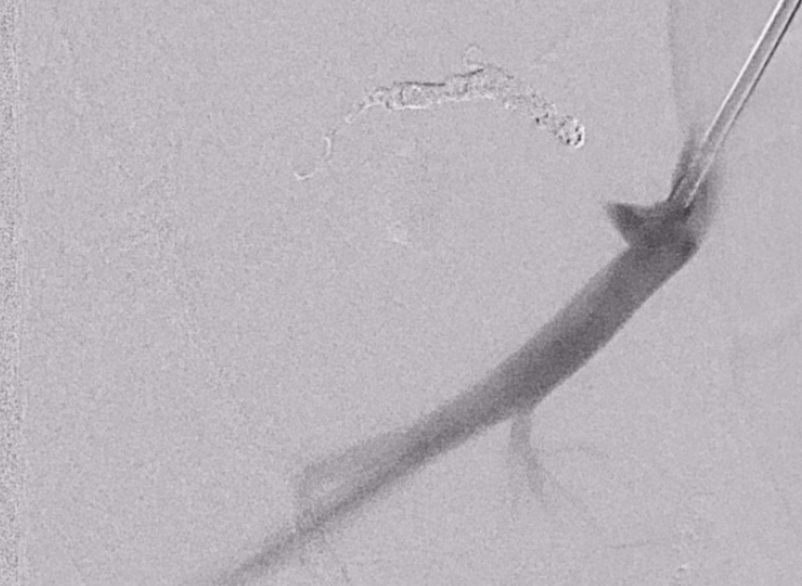

Initial experience with Penumbra Coil 400 versus standard coils in

From jnis.bmj.com

Initial experience with Penumbra Coil 400 versus standard coils in What Are Penumbra Coils Made Of the penumbra embolization platform consists of ruby coil®, pod® (penumbra occlusion device), and packing coil, with newer iterations like ruby coil lp and packing coil lp offering extended lengths (up to 70 cm) and soft Ruby ® coil lp & packing coil lp offer the same technology as penumbra’s large volume system. the penumbra lp coil system is. What Are Penumbra Coils Made Of.